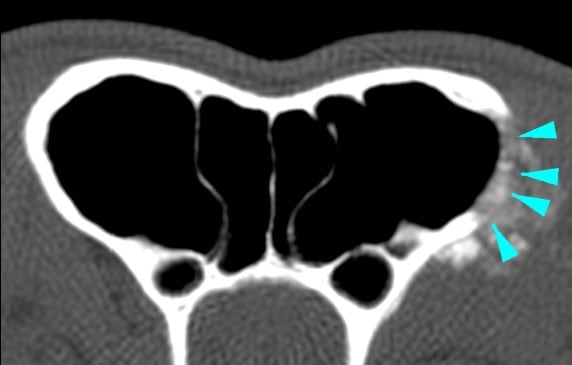

A CT scan of the head revealed the presence of a soft tissue space-occupying lesion of approximately 3 cm in diameter, arising from the orbital part of the left frontal bone (green arrowheads). The mass was laterally compressing the ipsilateral eye. A focal osteolytic process was observed at the level of the left zygomatic process of the frontal bone (light blue arrowhead).